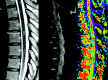

Purpose: Our aim was to study the fractional anisotropy (FA) variations and the fiber tracking (FT) patterns observed in patients with myelitis.

Material and methods: Fifteen patients with symptomatic myelitis and 11 healthy subjects were prospectively selected. We performed T2-weighted and diffusion tensor imaging on a 1.5T MR scanner. FA and apparent diffusion coefficient maps were computed in both healthy subjects and patients. In each patient, we performed FT to study pathologic aspects on this imaging method. FA data were analyzed by using z-scores.

Results: For the healthy subjects, averaged FA values ranged from 0.745 to 0.751. All abnormal areas seen on T2-weighted imaging had a significantly decreased FA value. In 9 patients (60%), FA maps showed decreased FA areas, whereas T2-weighted imaging findings were normal. These areas matched the neurologic deficit in 33%. Eighty percent of patients had multiple decreased FA areas. Five patients (33%) had increased FA values in normal T2-weighted areas.

Conclusion: We observed specific FA and FT pattern variations in patients with myelitis.